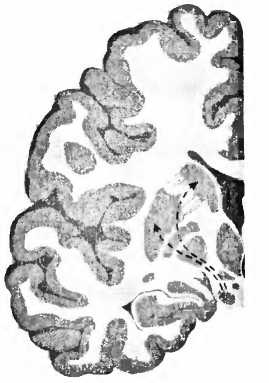

Если трансплантация зародышевой мозговой ткани прошла успешно, какие свойства могут быть приобретены от донора? Для болезни Паркинсона характерно отмирание дофаминовых клеток в черной субстанции (substantia nigra) мозгового ствола (рис. 23). При вскрытии эта область мозга из-за пигментации клеток, вырабатывающих дофамин, выглядит как проходящая через мозговую ткань черная лента. И если эти клетки мертвы, их сразу же видно, как, например, при болезни Паркинсона. Тогда клетки не могут больше иннервировать полосатое тело (стриатум), моторную область в центре мозга, то есть снабжать ее нервными волокнами и управлять ею. Из-за недостатка в стриатуме дофамина возникают типичные для этой болезни расстройства движения. Что может быть логичнее, чем лечить эту болезнь заменой умерших клеток? В1987 году в ведущем профессиональном журнале The New England Journal of Medicine [89] появилась статья мексиканского врача Мадрасо, в которой он сообщал о поразительном улучшении у больного паркинсонизмом после аутотрансплантации ткани дофаминсодержащих клеток надпочечников в хвостатое ядро (nucleus caudatus, рис. 23). В ближайшие два года сообщение привело к лавине из 200 подобных трансплантаций. Но операция оказалась неэффективной, и в течение двух лет после нее 20 % пациентов умерли. Исследование мозга умерших показало, что трансплантированная из надпочечников ткань в мозге не прижилась. В стриатуме были видны только шрамы. Многообещающие результаты Мадрасо были основаны, вероятно, на непрофессионально проведенных исследованиях в сочетании с эффектом плацебо (см. XVII.4). С 1988 года больным паркинсонизмом вместо аутотрансплантации в стриатум ткани надпочечников производят пересадку дофаминсодержащих клеток фетального мозга. Для достижения эффекта ткань должна быть взята у плода возрастом от 6 до 8 недель. Позитронно-эмиссионная томография показала, что при жизни наличие трансплантата можно было установить в мозге примерно 85 % прооперированных пациентов. В стриатуме мозга скончавшегося пациента дофаминсодержащие клетки, связанные с клетками мозга реципиента, были найдены через 16 лет после операции. Но иногда всё же новые дофаминовые клетки также перенимают симптомы болезни Паркинсона. Тот факт, что болезнь иногда переходит на трансплантат, является, возможно, причиной последующего ухудшения состояния пациентов, которые сначала выиграли от операции. Для имплантации необходим материал от четырех эмбрионов. Получить такой материал нелегко, поскольку источником его служит аборт, причем должно быть получено предварительное согласие женщины на трансплантацию. Поэтому сейчас возлагают большие надежды на эмбриональные стволовые клетки как альтернативный источник для трансплантации, так как при их выращивании можно дифференцировать дофаминовые нейроны. В настоящее время, впрочем, эта терапия обладает многими недостатками и таит в себе немало опасностей. Зафиксирован случай, когда у больного через 4 года после инъекции стволовых клеток в мозжечок образовалась опухоль мозга. Из стволовых клеток в принципе может вырасти что угодно, в том числе и опухоль. ![]() ![]() NCSN норма ![]() болезнь Паркинсона Рис. 23. При болезни Паркинсона пигментированные черным клетки, производящие дофамин в черной субстанции (SN), умирают и уже больше не могут управлять моторной областью — полосатым телом стриатумом (Р — putamen, скорлупа; NC — nucleus caudatus, хвостатое ядро). Трансплантация зародышевых дофаминовых клеток в мозг больных паркинсонизмом может иметь определенный успех, так как тогда их лекарство, леводопа, требуется им в меньшем количестве, и к тому же двигательные расстройства снижаются. 11о об окончательном выздоровлении речь не идет, и результаты варьируются. Кроме того, и позитивное воздействие, и побочные эффекты трансплантации те же, что и у леводопы. Примерно в 15 % случаев осложнения при трансплантации проявляются в виде нарушений движений (дискинезии), что возникает также и при приеме леводопы. Проводились плацебо-контролируемые исследования, когда половина пациентов (которые не знали, к какой именно группе они относятся), хотя и были оперированы, не получили трансплантата. Через два года, в том, что касается двигательных расстройств, не было никакой разницы между мнимо оперированными пациентами и пациентами с трансплантатом. В итоге убедительных результатов до сих пор не имеется (см. XVII.4). |